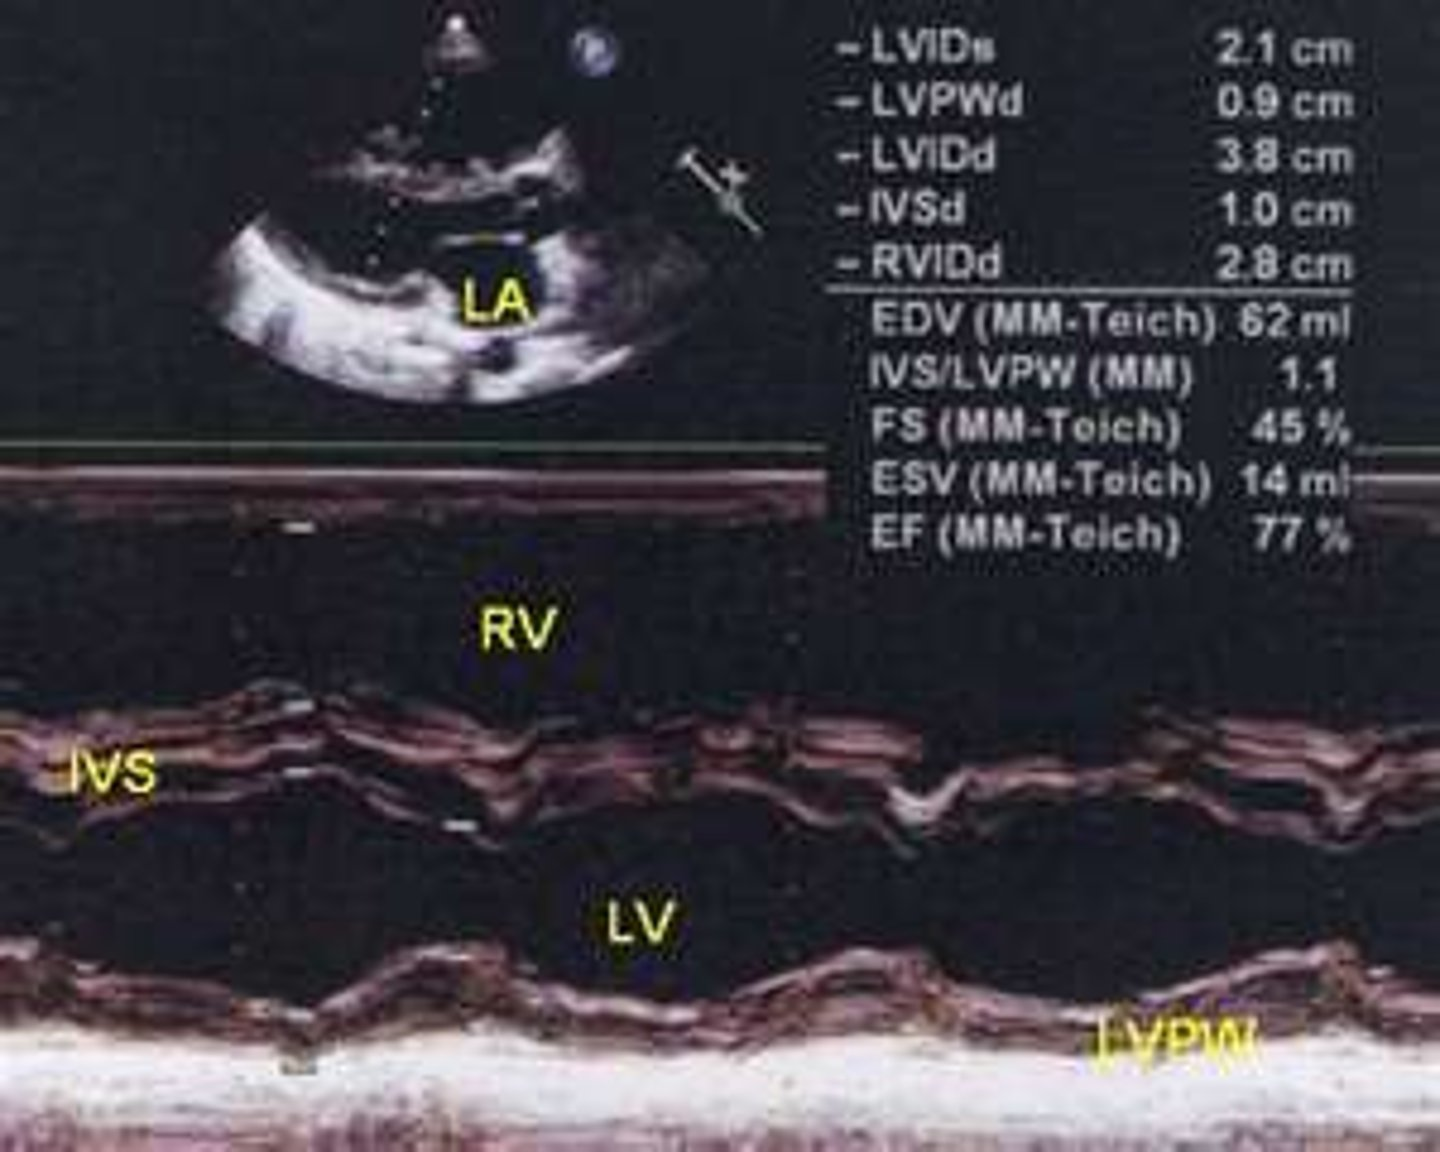

thickening of the septal and/or posterior wall, can be symmetrical or asymmetrical

LV hypertrophy